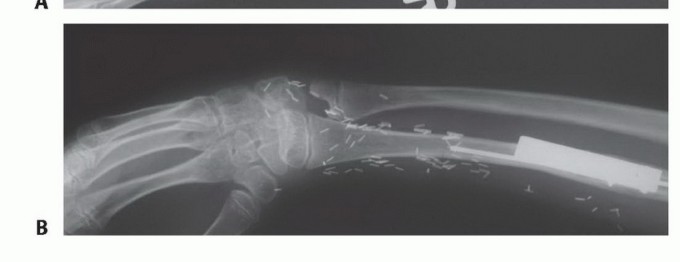

- التصوير المقطعي المحوسب (CTA): يُستخدم التصوير المقطعي المحوسب (FIG 4C) عندما تكون الأوعية الدموية غير واضحة، حيث يوفر صورًا مفصلة للأوعية الدموية في المنطقة المستقبلة.

تصوير عيوب العظام

- ج. إعادة بناء مقطعي محوسب إكليلي للساعد البعيد يُظهر ساركوما عظمية في الكعبرة البعيدة.